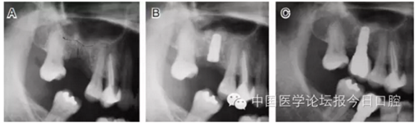

病例4 植入骨替代材料(圖6)

圖6